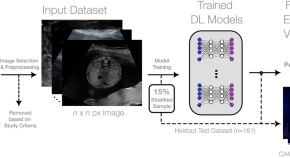

Differential diagnosis of thyroid nodules using heterogeneity quantification software on ultrasound images: correlation with the Bethesda system and surgical pathology

- Young Jae Ryu

- Jin Woong Kim

- Tae-Hoon Kim

Deep learning prediction of renal anomalies for prenatal ultrasound diagnosis